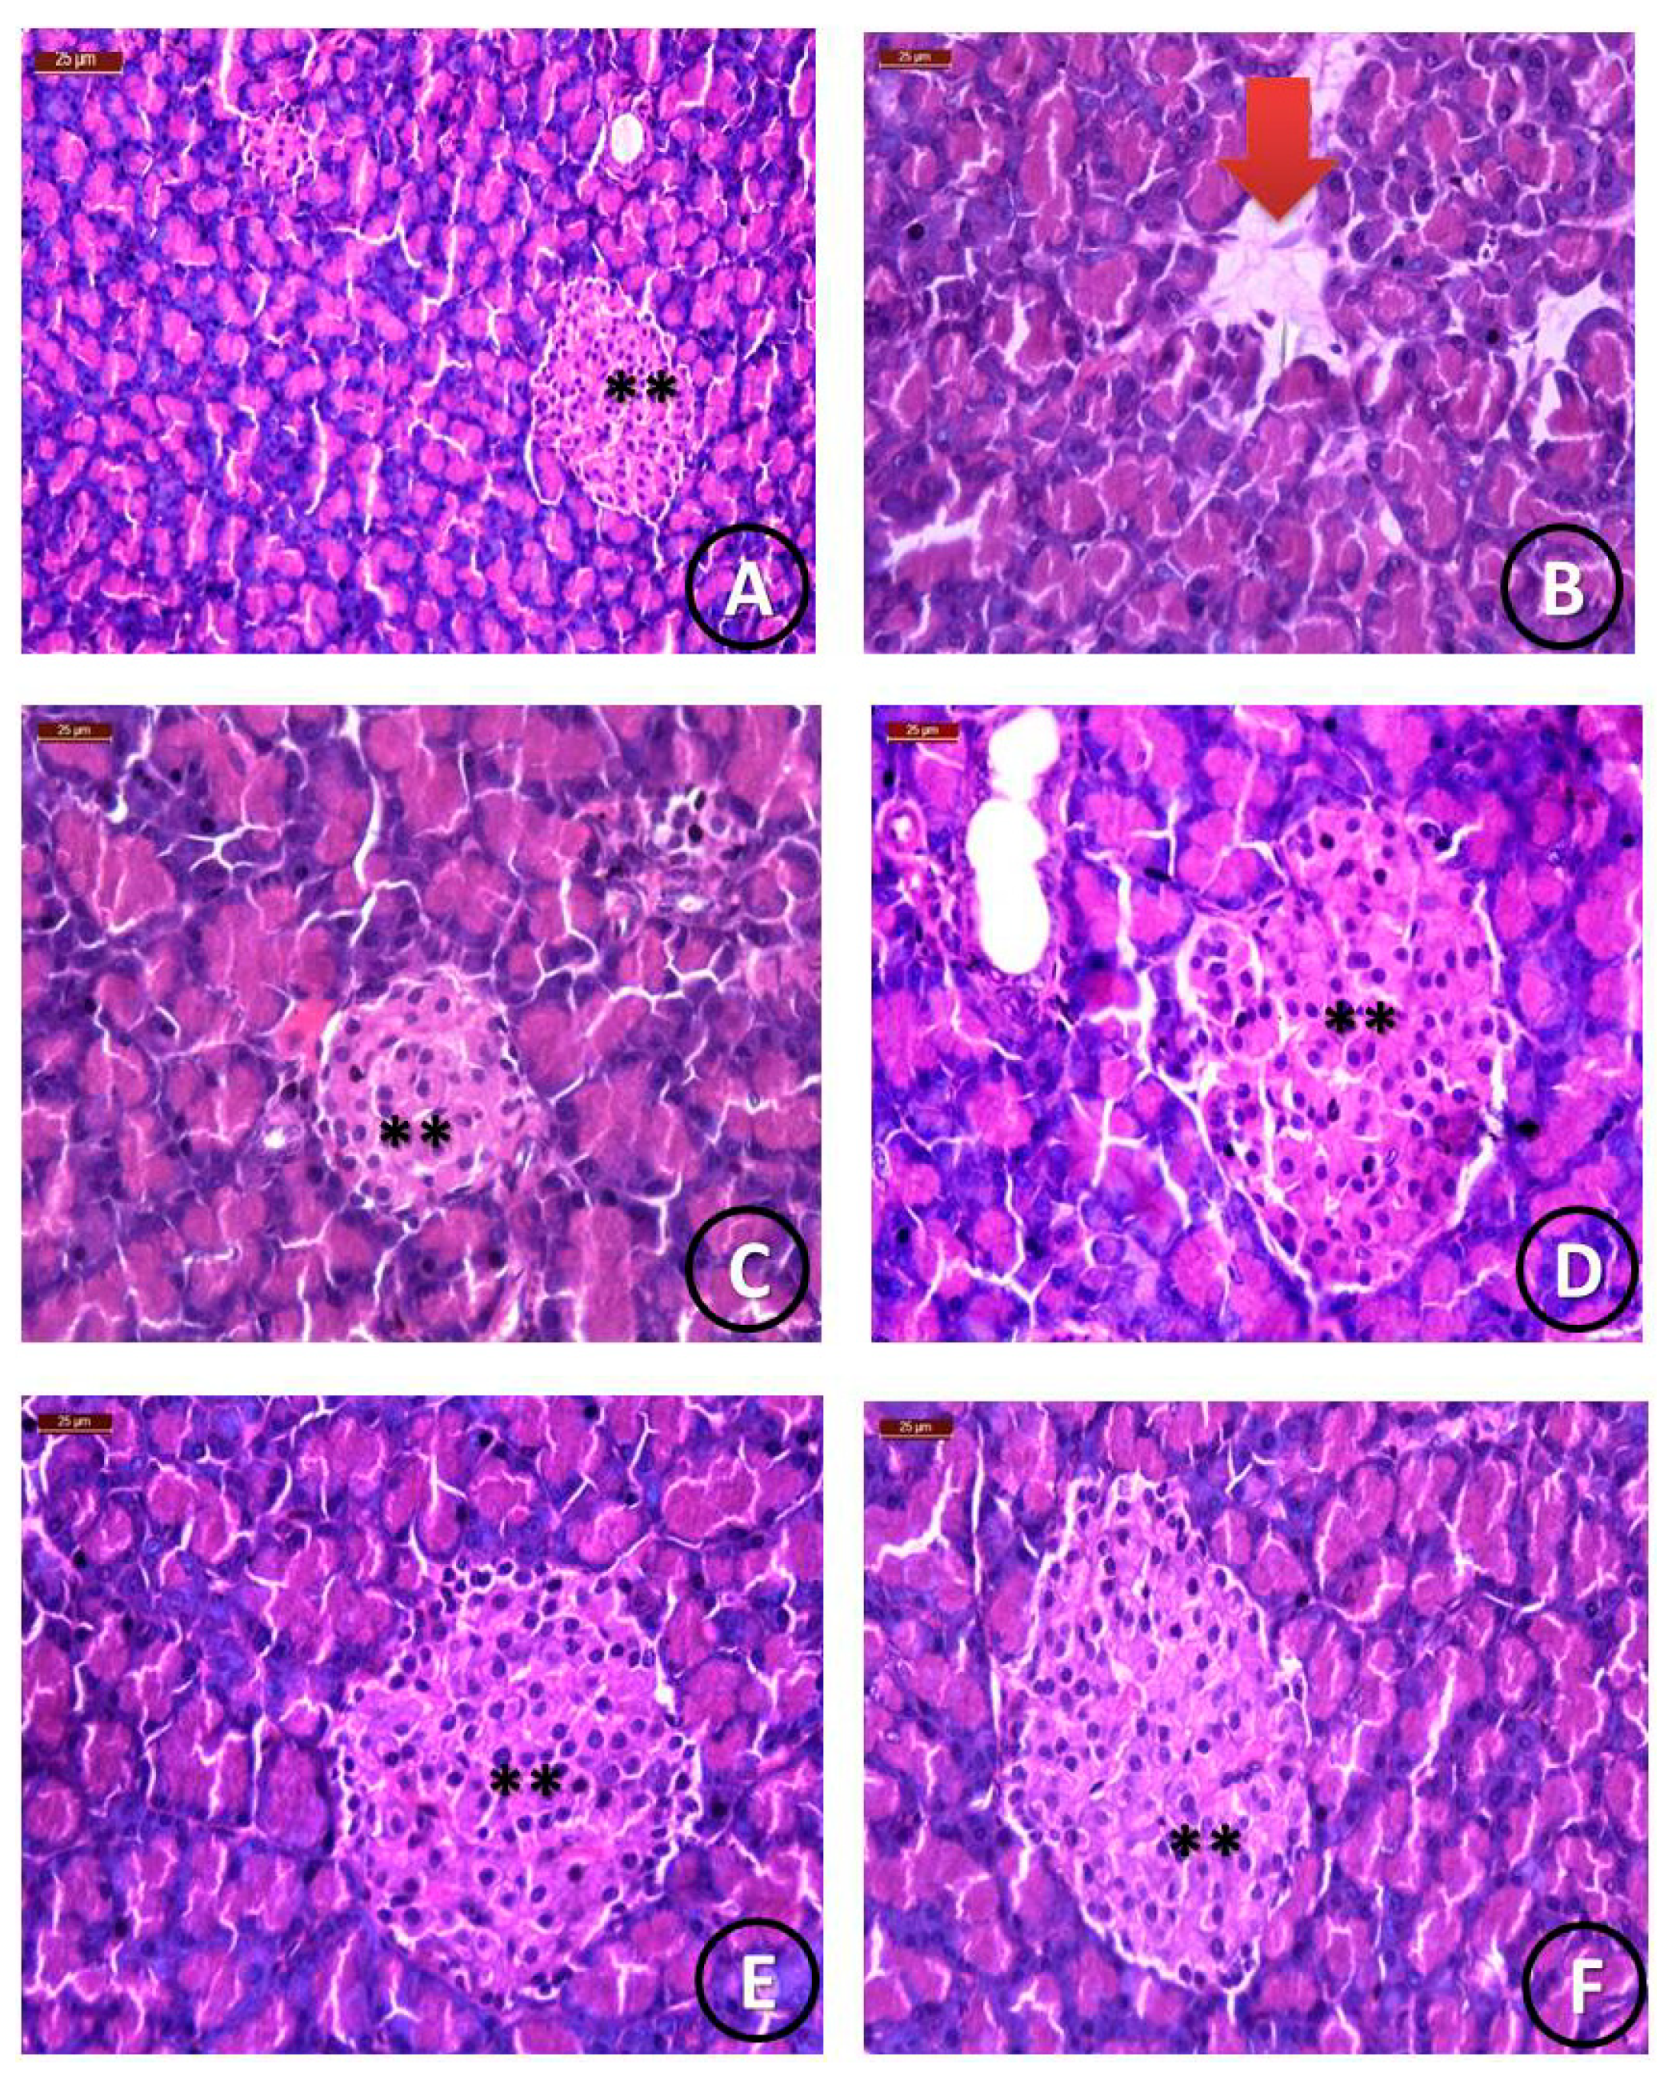

| Groups | Pancreatic Parenchyma | Islets of Langerhans Size | ||||

|---|---|---|---|---|---|---|

| Normal | Detached | Normal | Reduced | Mild | Enlarged | |

| Group 1 (Control) | 90% | 0% | 90% | 0% | 0% | 0% |

| Group 2 (STZ) | 0% | 90% | 0% | 90% | 25% | 0% |

| Group 3 (STZ +STG) | 80% | 25% | 80% | 0% | 80% | 80% |

| Group 4 (STZ+ STG/Cu) | 90% | 0% | 90% | 0% | 25% | 90% |

| Group 5 (STZ+ STG/Mg) | 90% | 0% | 90% | 0% | 25% | 90% |

| Group 6 (STZ+ STG/Zn) | 90% | 0% | 90% | 0% | 25% | 90% |

| Group 7 (STZ+ STG/Ca) | 90% | 0% | 90% | 0% | 25% | 90% |

| Group 8 (STZ+ STG/Cr) | 90% | 0% | 90% | 0% | 25% | 90% |

| Group 9 (STZ+ STG/Se) | 90% | 0% | 90% | 0% | 25% | 90% |